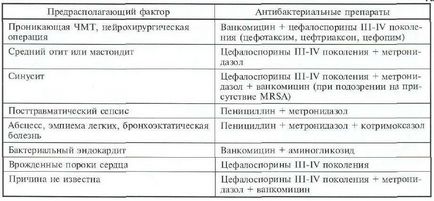

A kezelés EDS párhuzamosan sebészetileg-MI előírt módszerek antibakteriális pre-Paratov. Megszerzését megelőző adatokat a gerjesztő-Empi-paraméter terápia, attól függően, hogy a lehetséges oka, 2. táblázatban mutatjuk be (1). Miután identitás-kórokozó-azonosítás-kezelés folytatása oldva vagy korrigálására a etiológia.

Táblázat 22-2. Empirikus antibiotikum terápia EDS